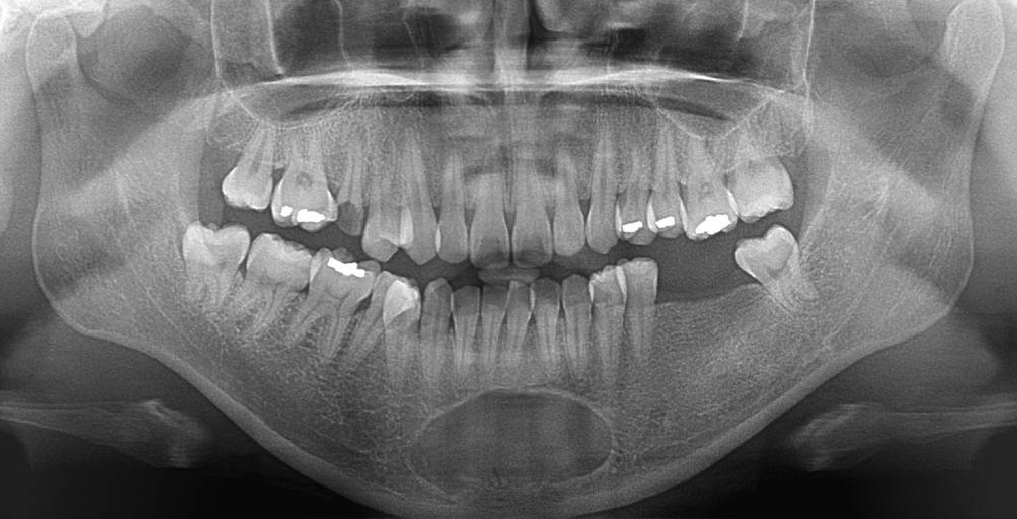

32세 여성 환자의 파노라마방사선영상에서 하악 전치부 낭이 관찰되어, 정확한 진단을 위하여 본원에 의뢰되었다. 특별한 임상증상은 없었다. 파노라마방사선영상에서 하악 우측 제1소구치에서 좌측 제1소구치 치근하방에 경계가 명확하고 피질골성 변연을 가진 타원형의 방사선투과상이 관찰되었다(Fig. 1). 방사선투과상은 해당치아들과는 무관하여 치근단낭이 배제되었고, 단순골낭의 가능성을 염두에 두고 콘빔CT 검사를 시행하였다. 콘빔CT에서 중심성 골내 병소가 아닌 악골의 순측에서 설측으로 함몰된 변연성 병소가 관찰되었다(Fig. 2). 병소의 경계는 매우 평활하였고, 단면상에서는 넓은 접시모양처럼(Fig. 3), 악골 절단면상에서는 반달모양처럼 함몰되어 있었다(Fig. 4). 설측 피질골은 비박되어 있었으나 천공은 관찰되지 않았다. 함몰된 부위는 공기가 아닌 연조직의 방사선투과상으로 채워졌으나, 콘빔CT에서는 대조도가 낮아서 연조직간의 감별이 가능하지 않았다(Fig. 5). 관찰된 턱 끝 부위의 골 함몰이 해부학적 변이인지 아닌지를 감별하기 위하여 환자의 과거 병력을 알아보았다. 환자는 2년 전에 턱 끝 부위에 미용 필러 시술을 받았다고 하였다. 방사선영상소견과 문진결과를 토대로, 미용 필러와 관련된 골흡수를 의심하였다. 이후 외과적으로 미용 필러 제거와 함몰된 부위에 골이식이 시행되었다. 수술 중에 육안으로 남아있는 미용 필러와 작은 석회화 물질들이 확인되었다. 수술 후 생검에서 다핵거대세포와 결절석회화가 관찰되었고, 피부석회화(calcinosis cutis)가 의심된다는 결과를 받았다. 이상의 술 전 검사 및 술 후 소견을 종합하여, 파노라마방사선영상에서 관찰된 방사선투과상은 치성낭이나 해부학적 변이가 아니고 미용 필러에 의한 하악골 순측 골흡수로 최종 진단되었다.

Panoramic view. A well-defined, corticated, oval-shaped radiolucency was observed in the periapical region of the mandibular right to left first premolars on panoramic radiography.